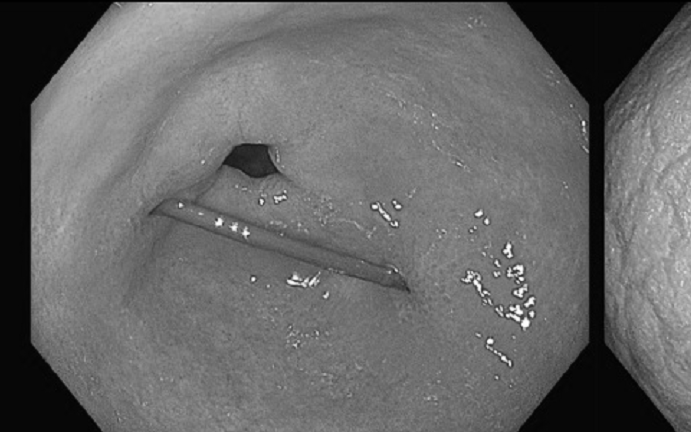

Người phụ nữ đau bụng thốc lên ngực, bác sĩ gắp ra thứ "đáng sợ" ĐỌC NGAY